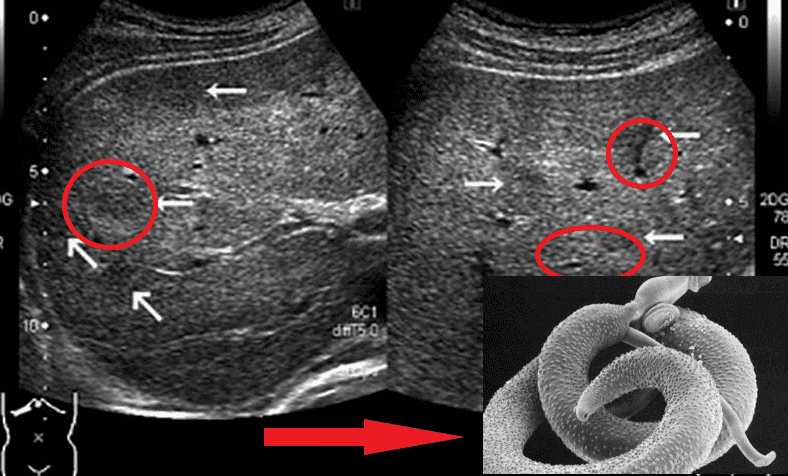

Представниками гельмінтів, що вражають життєво важливі органи, є Taenia solium, ехінокок (Echinococcus granulosus), трихінела (Trichinella spiralis). Ехінокок являє собою личинкову стадію гельмінта з роду Echinococcus. І це далеко не всі види паразитів, здатні убити людину.

О.Ю. Гришин: Так воно і є насправді. Практично в 90% випадків, коли я роблю розтин, бачу страшну картину. Тіла померлих кишать паразитами! І я спостерігаю їх не тільки в шлунково-кишковому тракті, як багато хто думає. Паразити часто живуть у легенях, серці, печінці й навіть у мозку! Їхні колонії населяють внутрішні органи, а личинки харчуються тканинами живих людей!

Я працюю патологоанатомом багато років. Я бачив таке, що волосся стає дибки! Люди недооцінюють небезпеки, вони думають, що паразити - це глисти, які живуть у кишках. Але це не зовсім так. Існує величезна кількість видів паразитів. Наприклад, є мікроскопічні, але дуже токсичні. Вони отруюють ваш організм, проникають у кров, у серце, виснажують його своїми токсинами, призводять до ішемії, серцевої недостатності, гіпертонії, і, як наслідок, - інфарктів та інсультів. Вони оселяються в легенях, печінці, проникають у мозок і навіть живуть в очах!